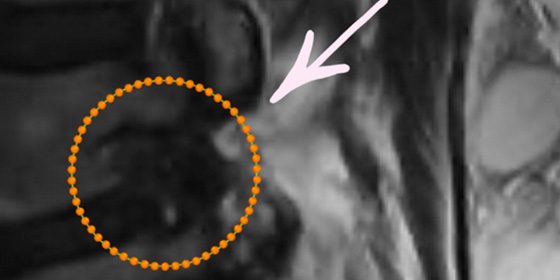

Imagem 1: Hérnia de disco foraminal L4-L5 à direita.

Imagem 2: Hérnia de disco – corte axial da rm.